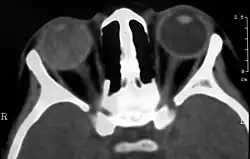

Computed Tomography image of a patient with Coats' disease, showing total exudative retinal detachment in the right eye

Imaging studies such as ultrasonography (US), Computerized Tomography (CT) and Magnetic Resonance Imaging (MRI) can aid diagnosis. On ultrasound, Coats' disease appears as a hyperechoic mass in the posterior vitreous without posterior acoustic shadowing; vitreous and subretinal hemorrhage may often be observed.[8][9]

On CT, the globe appears hyperdense compared to normal vitreous due to the proteinaceous exudate, which may obliterate the vitreous space in advanced disease. The anterior margin of the subretinal exudate enhances with contrast. Since the retina is fixed posteriorly at the optic disc, this enhancement has a V-shaped configuration.[2]